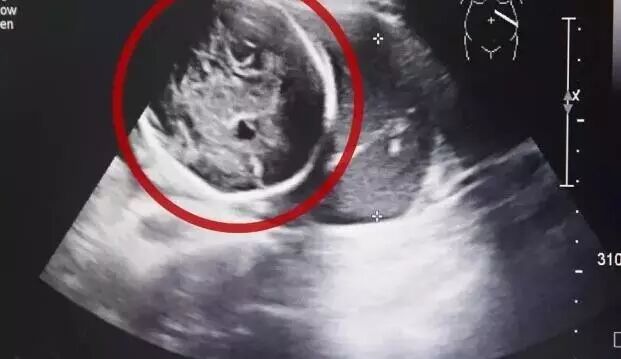

B超检查,小芳竟然已经怀孕了,而且胎儿已经长到了6个多月!但是让人吃惊的是胎儿并没有长在子宫里,而是长在了腹腔内。

医生确诊小芳为腹腔妊娠”,也就是宫外孕的一种,是发病率约为1:15000,母体死亡率约为5%,胎儿存活率仅为1%,这样的罕见妊娠竟然发生在了她的身上,医生和小芳都很震惊,而且小芳已经出现肚子疼痛,情况十分紧急。